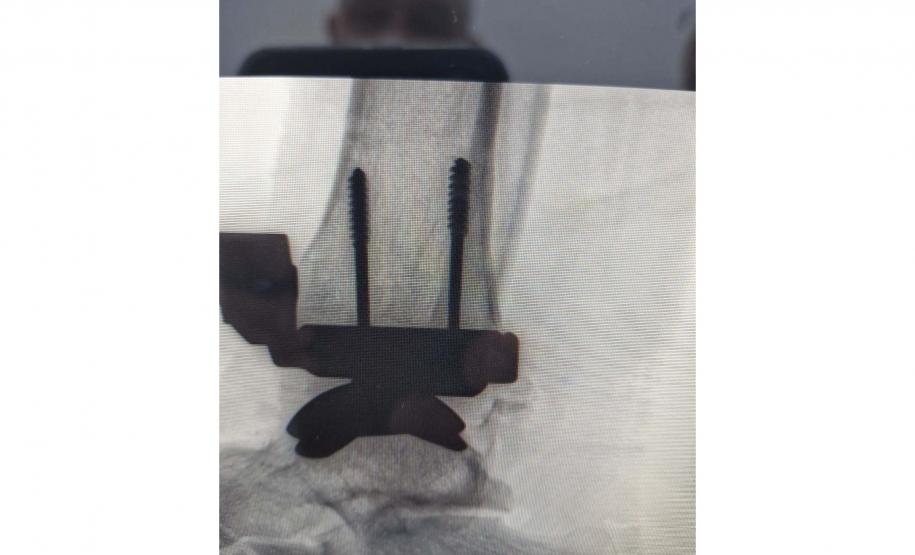

Um procedimento complexo e bastante moderno foi realizado no Paraná pela primeira vez por meio do Sistema Único de Saúde (SUS), no Hospital do Trabalhador, em Curitiba. Trata-se da cirurgia de artroplastia de tornozelo, feita com sucesso, que substituiu a articulação de um paciente por uma prótese total, possibilitando a restauração da mobilidade e o fim da dor crônica.

A cirurgia foi realizada no mês de setembro e é um marco pelo resultado alcançado. O procedimento de colocação de uma prótese total devolve a possibilidade de se fazer movimentos como agachar ou subir uma escada, e de acabar com as dores crônicas de quem não pode sequer pisar no chão.

A cirurgia durou cerca de três horas com a equipe do médico Bruno Arnaldo Bonacin Moura. É considerada bastante complicada, pois requer treinamento altamente especializado para cortes ósseos, alinhamento dos componentes da prótese e equilíbrio do tornozelo. “Qualquer desvio milimétrico pode comprometer o resultado”, ponderou o médico.

DOR CONSTANTE – O paciente operado pela equipe é Heitor de Oliveira Tedesco. Ele foi vítima de um acidente de trabalho em 2022 e teve fratura exposta no tornozelo, o que obrigou uma cirurgia de emergência, com a colocação de seis pinos e uma placa.

Em fevereiro deste ano, o médico que o atendia optou por tirar os pinos e a placa e fez o pedido de uma nova cirurgia, quando apareceu a opção por uma prótese. Após a cirurgia, ele vem apresentando recuperação dentro do esperado pelos médicos, com melhora na movimentação, sem dor significativa e conseguindo retomar suas atividades de forma segura.